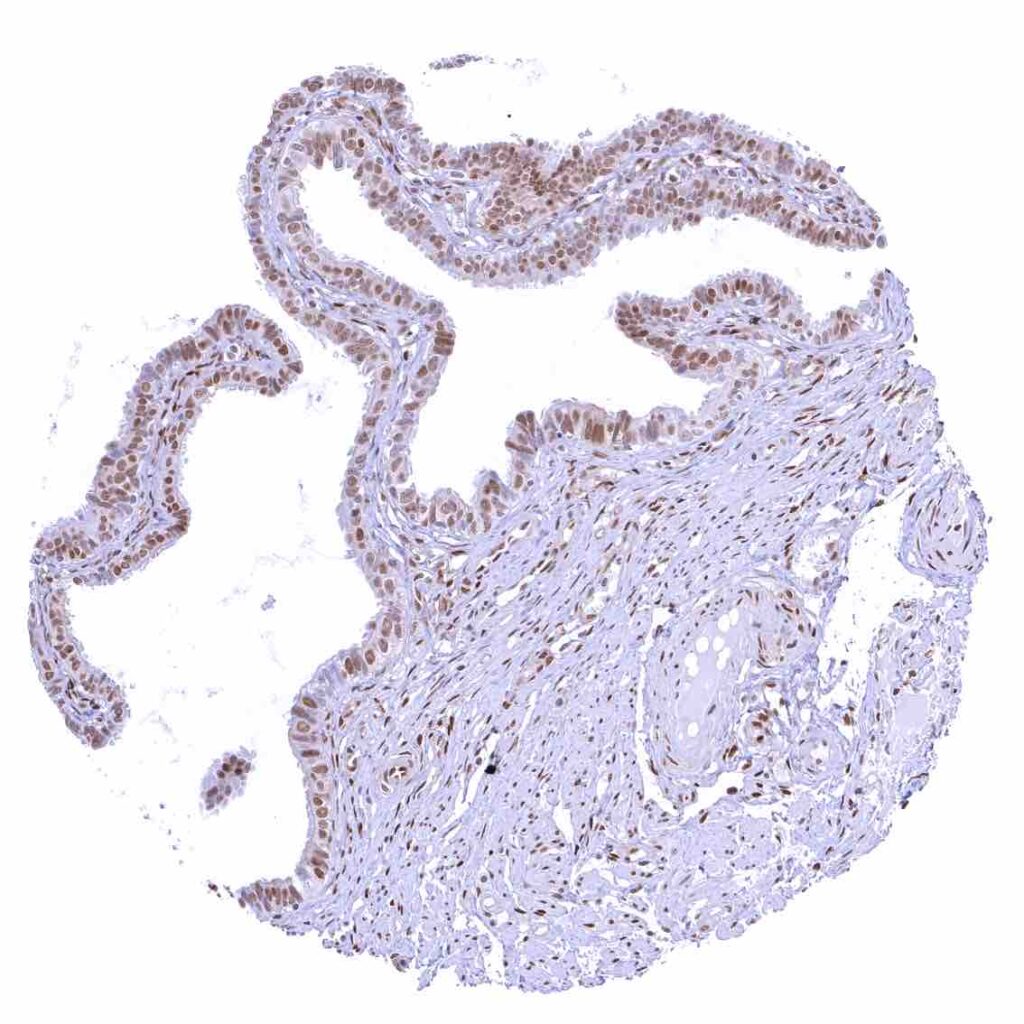

Fallopian tube, mucosa

Uterus, endocervix – Nuclear p27 staining is variable in the endocervix. It is positive in all epithelial cells in this sample.

Uterus, endocervix.jpeg